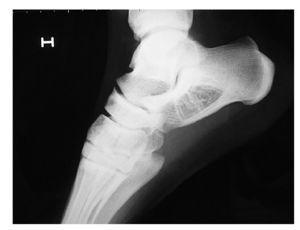

Dado el diagnóstico, se realiza tomografía computarizada (TC) para valorar especialmente el estado de las corticales óseas (fig. 3).

Figura 3 Imágenes coronal y sagitales en la TC.

La TC muestra una lesión osteolítica con áreas de densidad similar al tejido adiposo y extensas calcificaciones u osificaciones. Las corticales se encuentran perfectamente conservadas y sin riesgo de rotura.